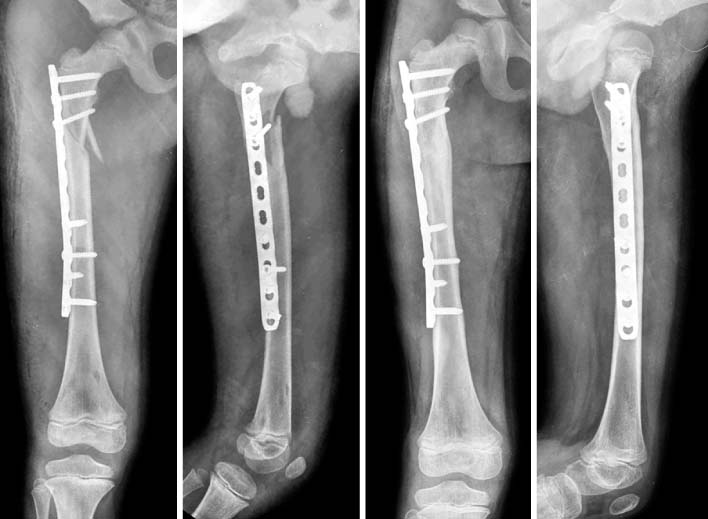

Fig. 5

These are the sequence of operatingprocedure in the suggested patient of Fig. 1. After the temporary reduction of femoral fracture with flexible nails, the plate was introduced through the submuscular tunnel. Then, the locking screws were fixed at the proximal and distal sides of the plate. The fracture site was not open to preserve the biology. The flexible nail makes an easier reduction of fracture, which facilitates the minimally invasive plate osteosynthesis (MIPO) procedure.

Fig. 5 These are the sequence of operatingprocedure in the suggested patient of Fig. 1. After the temporary reduction of femoral fracture with flexible nails, the plate was introduced through the submuscular tunnel. Then, the locking screws were fixed at the proximal and distal sides of the plate. The fracture site was not open to preserve the biology. The flexible nail makes an easier reduction of fracture, which facilitates the minimally invasive plate osteosynthesis (MIPO) procedure.